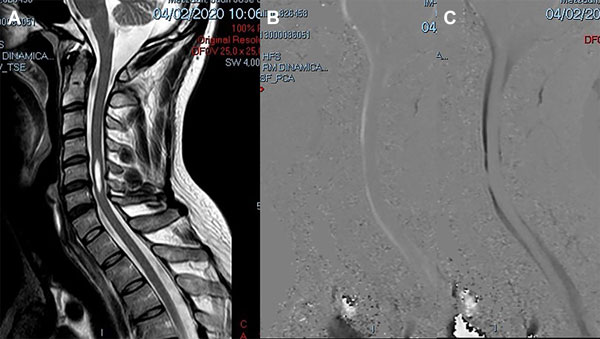

Un varón de 38 años de edad consultó por haber padecido una cérvico braquialgia derecha 30 días antes. En el momento de la consulta sus síntomas habían desaparecido y el examen neurológico fue normal. La RM mostró discopatías cervicales múltiples con una dilatación quística en la médula cervical a nivel C5-C6 que no tomaba el contraste con gadolinio (Figura 6A). Para profundizar el diagnóstico diferencial se realizó una RM en contraste de fase para medir la velocidad del LCR a nivel del canal cervical. La velocidad medida fue de 11 cm/seg (Figura 6B-C). Se hizo el diagnóstico de SM espinal primaria causada por una discopatía cervical a nivel C5-C6. Como el paciente estaba asintomático sólo se indicó control periódico. En su última evaluación, 2 años después, la situación clínica e imagenológica no había cambiado por lo que se mantuvo la misma conducta.

Figura 6: Caso 4. A: RM de columna cervical en plano sagital ponderada en T2 que muestra una cavidad intramedular entre C5 y C6 compatible con siringomielia. B: Estudio de dinámica de LCR que muestra una imagen de magnitud en fase anterógrada con señal hiperintensa el flujo en sístole con disminución del pasaje del LCR en C5-C6. C: Estudio de dinámica de LCR que muestra una imagen de magnitud en fase retrógrada con señal hipointensa el flujo en diástole con la alteración del pasaje de LCR a nivel C5-C6.